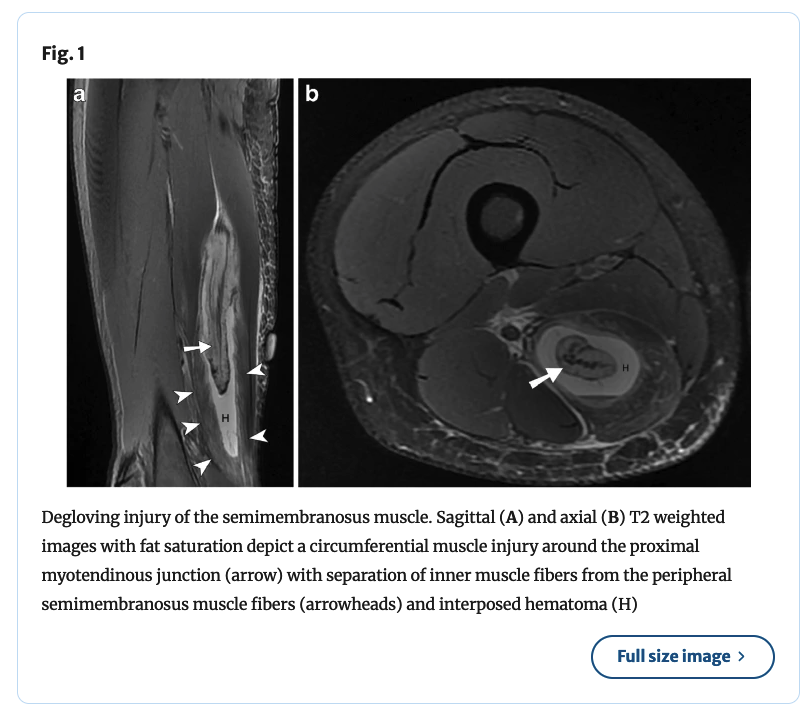

⚽️Degloving intramuscular injuries of the semimembranosus and adductor longus muscles in adolescent soccer players... Degloving muscle injury was described for the rectus femoris where the inner bipennate component is dissociated from its superficial unipennate component. The

#ParisOlympics 🗼 Management of Hamstring and Rectus Femoris Tendon Injury in Elite Track and Field Athletes There is little debate on the relevance of thigh muscle injury in elite sports. Their incidence, impact on athletic as well as team performance, and tendency to recur